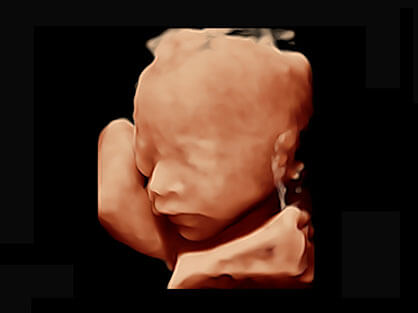

可同时显示组织结构表面和内部的轮廓信息,达到透视效果,为临床提供更丰富的诊断信息。

宽频带腹部凸阵探头和腹部容积探头、大角度腔内探头和腔内容积探头、独特的生殖专用曲柄探头,为妇产应用提供全面诊疗方案。

大角度腔内容积探头,可完整包络子宫及盆底结构,充分展示组织结构毗邻关系。